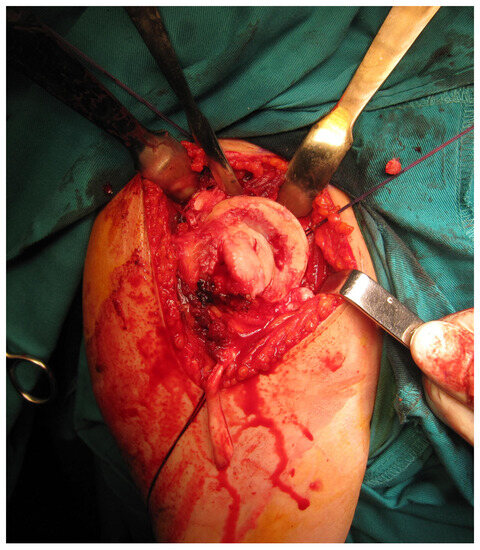

All femoral condyle osteochondral allografts were fresh-frozen and stored at −80 °C. They were tested for bacterial contamination, as well as serologically for hepatitis (A, B and C) and human immunodeficiency virus. On the day of surgery, the osteochondral grafts were thawed and submerged in 300 mL of saline solution with five ampoules of 120 mg gentamycin. Before placement, the grafts were washed with 500 mL of pure physiological solution. An oscillating saw was used to prepare the humeral head defect site for the osteochondral allograft. The dimensions of the lesion were carefully measured, and a similarly sized allograft was modeled accordingly (Figure 2 and Figure 3). Tenodesis of the long head of the bicep tendon was performed in all patients. Fixation of the allograft to the humeral head was achieved using two cancellous screws in four patients, while two Herbert screws [8] were used in the remaining sixteen patients, all placed subchondrally (Figure 4). After the shoulder joint was reduced into place, the reinsertion of the m. subscapularis was performed in its anatomical position (because osteotomy of the lesser tubercle was performed during the procedure). During the immobilization period, the m. subscapularis healed in its anatomical position. The shoulder joint capsule was sutured with absorbable sutures and the wound was closed in layers.

Figure 3. Osteochondral femoral allograft (photo from the personal archive of intraoperative photos of the author).